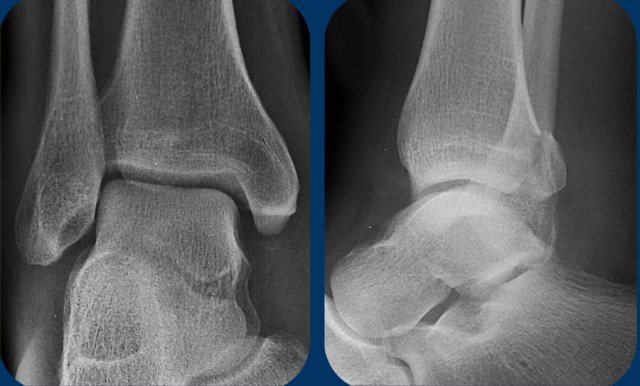

Click on the images to enlarge Click on the images to enlarge

Study the images.

Use the algoritm and ask yourself if it is a Weber A or B or that it could be a Weber C.

Then determine the stage.

Then continue for a discussion of this case.

1. At first sight it just looks like only a tertius fracture.

2. When we look at the algoritm, you can see, that a tertius can be found in a Weber B fracture in stage 3 and in a Weber C fracture in stage 4.

Since this patient doesn't have a Weber B, it must be a Weber C fracture. An isolated tertius fracture is very uncommon and probably does not exist.

3. Now we recognize the soft tissue swelling on the medial side, which is stage 1.

4. On the enlarge view we also recognize a small avulsion fracture.

Having detected stage 1 and 4 of a Weber C type of trauma mechanism, we now are sure that there must also be a stage 3, which is a high fibula fracture.